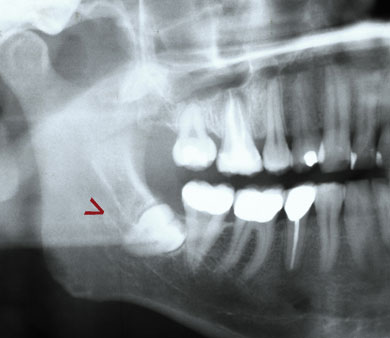

Lagebestimmung von verlagerten Zähnen

Im normalen Röntgenbild kann die genaue Lage nicht sicher festgestellt werden.

In unserem Fall hier lag ein Zahn zur Lippe hin (*) und ein Zahn im Gaumen (**). Mit diesen Informationen können wir minimalinvasiv und sehr schonend operieren!